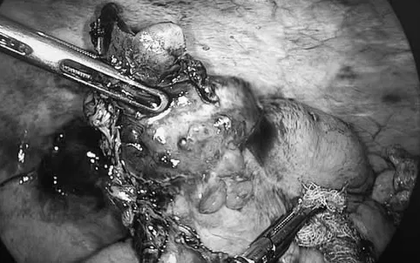

Phát hiện ung thư ruột thừa hiếm gặp khi mổ viêm ruột thừa

Bệnh viện 19-8 (Bộ Công an) phát hiện ung thư ruột thừa hiếm gặp trong ca phẫu thuật viêm ruột thừa cấp, kịp thời chuyển hướng mổ, giúp bệnh nhân ổn định sức khỏe.